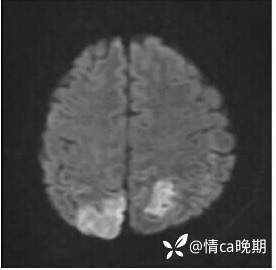

头颅MRI提示:①双侧顶枕叶急性脑梗塞;②左侧半卵圆中心小缺血灶。